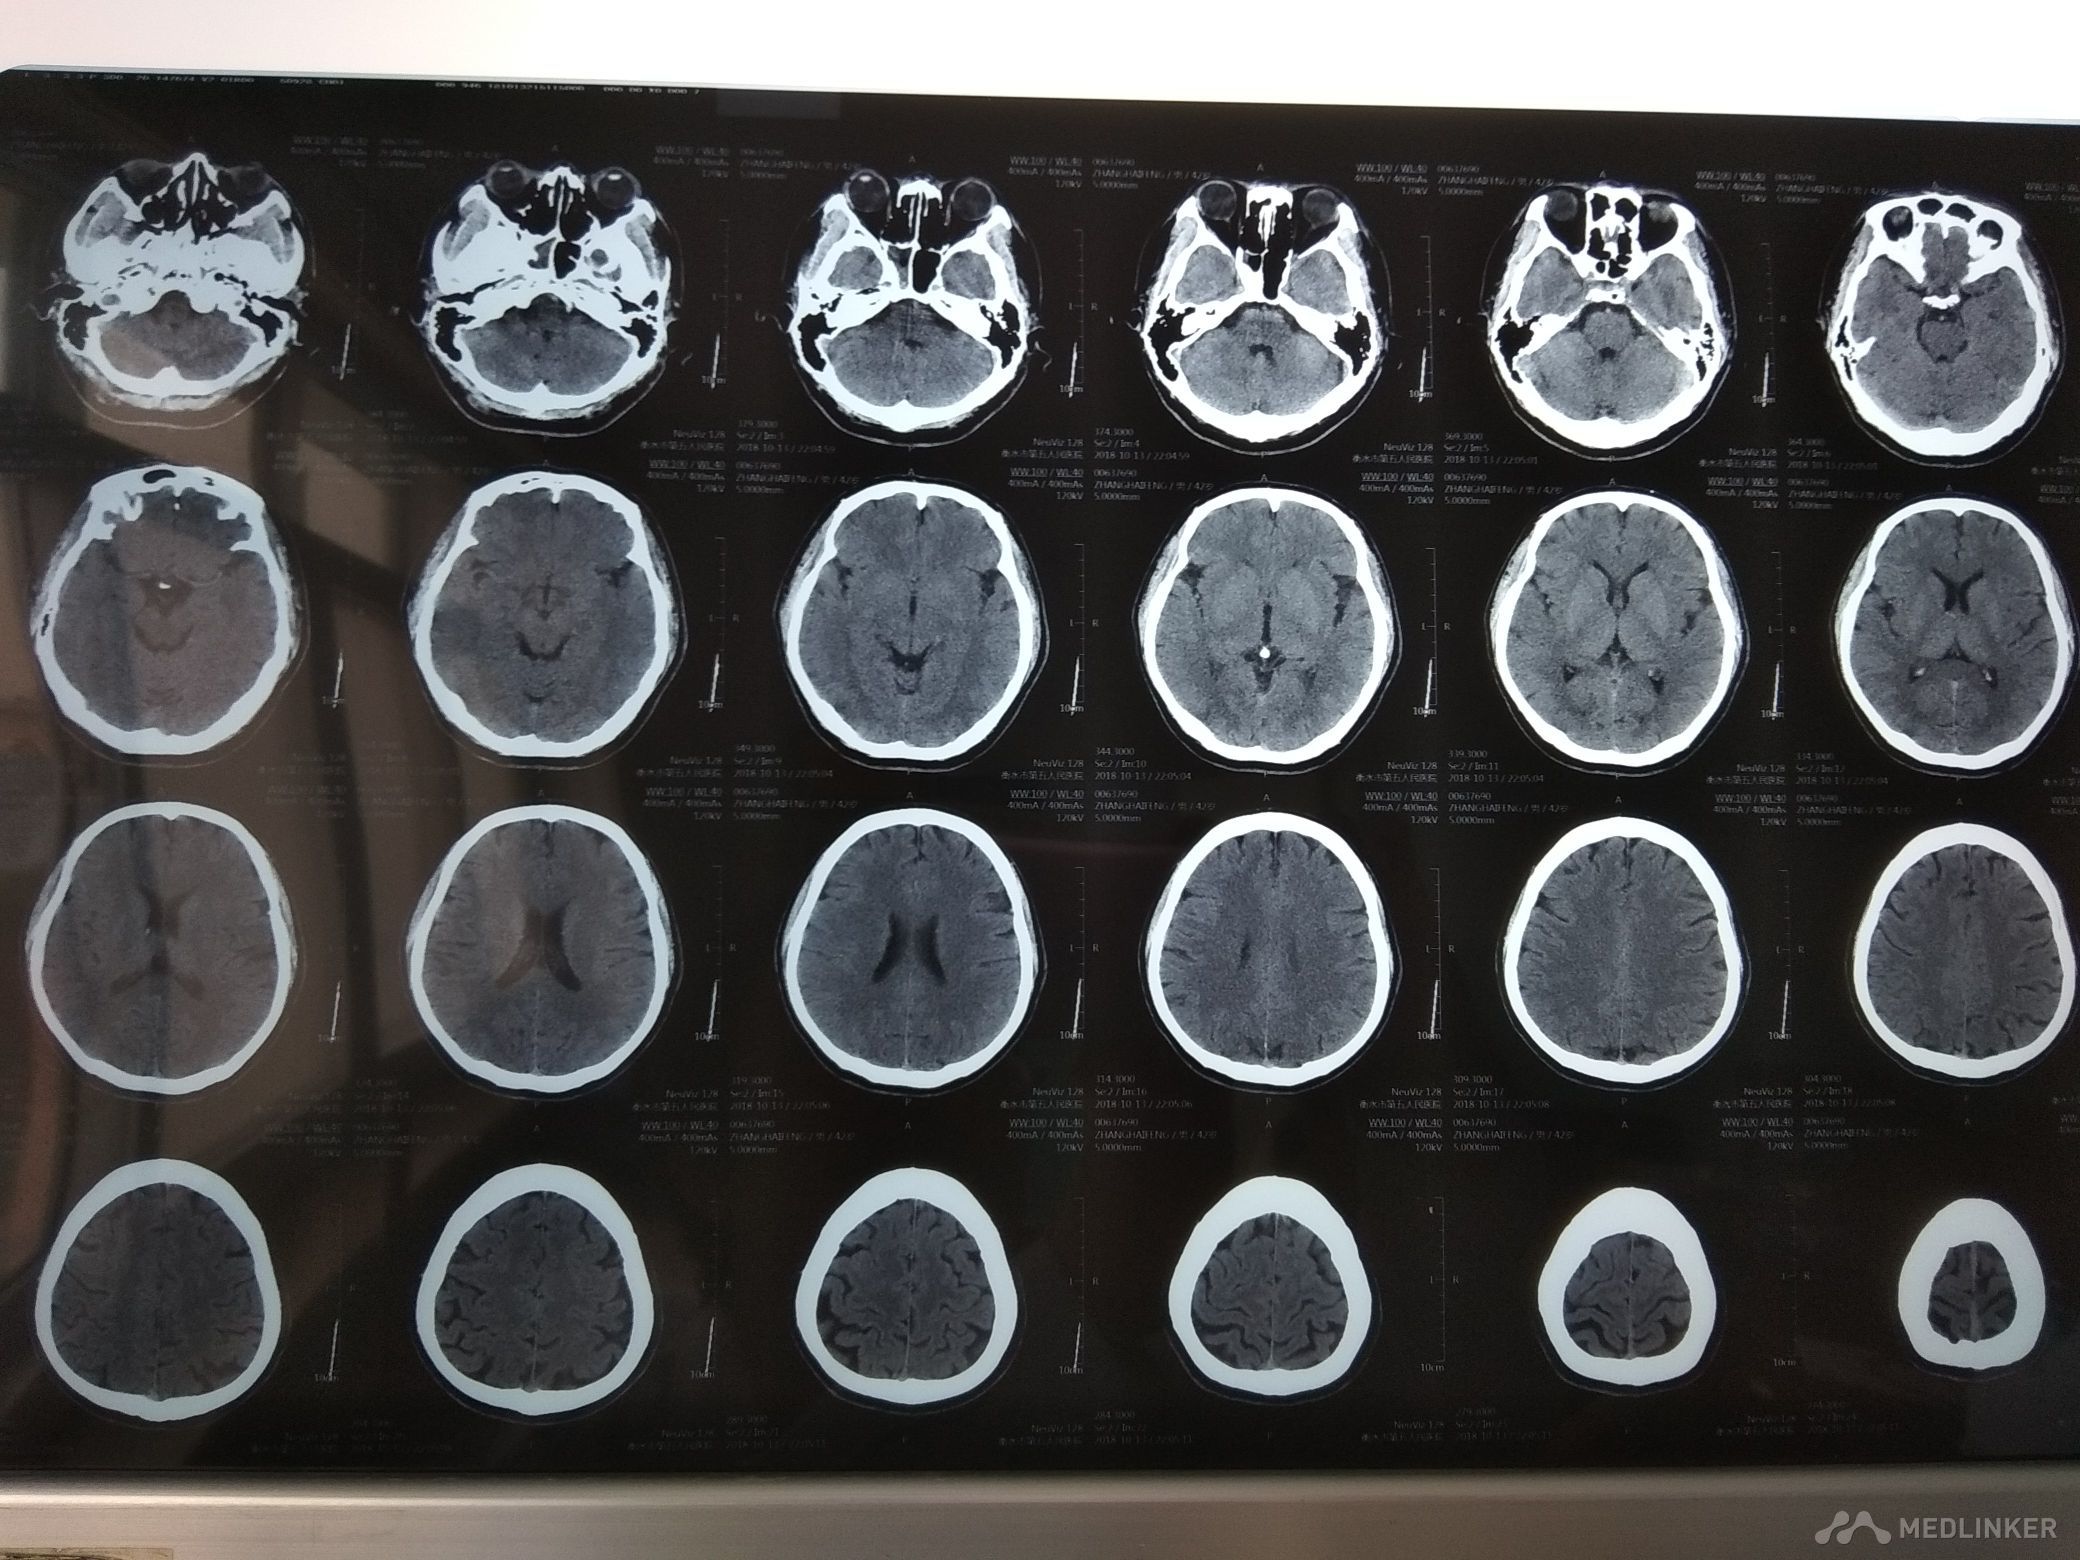

主诉 发作性左侧肢体无力1天余。病史 45岁男性患者,于入院前1天无明显诱因出现左侧肢体无力,左下肢明显,走路不稳。未予治疗,约3分钟缓解。无头晕头痛,无恶心呕吐,无肢体抽搐,无意识障碍,无尿便障碍。共发作2次,为求诊治,遂来我院,以“短暂性脑缺血发作”收入我科。 既往体健。吸烟饮酒史。

查体BP140/90mmHg,神清,语利,右利手,计算力,记忆力,定向力,理解判断力正常。鼻唇沟基本对称,伸舌稍偏右,四肢肌力5级,肌张力,腱反射适中对称,针刺觉两侧对称,共济检查较稳准,双侧病理征未引出。颈软,双下肢无水肿。肺心腹未见明显异常。 心电图大致正常。化验结果:血常规,血凝,电解质,肝肾功能,心肌酶,血糖,血脂,同型半胱氨酸正常。

诊断 短暂性脑缺血发作, 治疗 予阿司匹林抗血小板聚集,降脂稳定斑块,促进侧支循环建立,改善循环,营养神经等治疗。